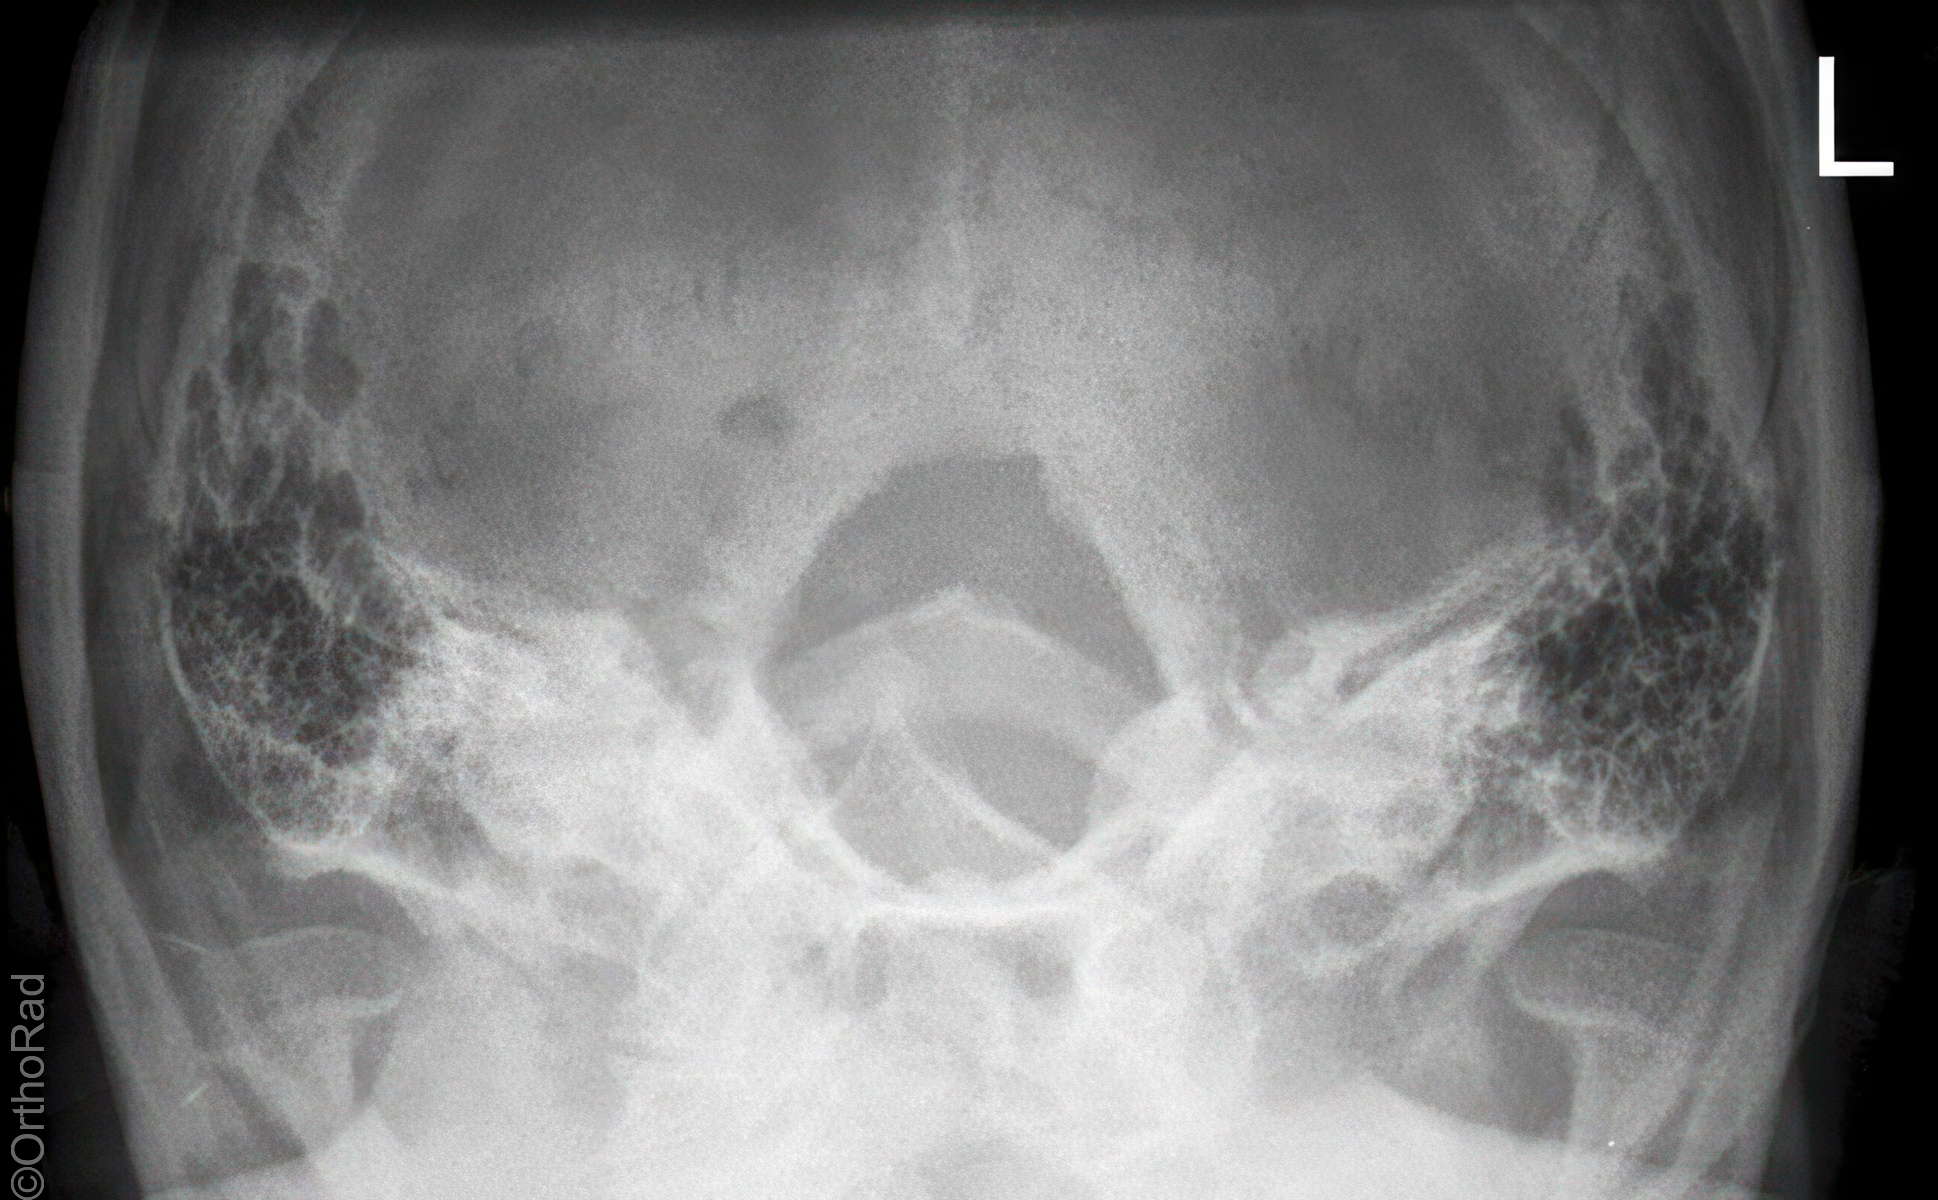

Felsenbein Vergleich (Altschul-Uffenorde)

Technik

• FDA: 1,15 m

• Ausgangsformat: 18/24 quer

• mit Raster

• Röhrenkippung: 30° bis 35° cranio-caudal

Lagerung

Patient in Rückenlage, Kopf mit 2 x 15° Keil unterpolstern, Doppel-Kinn! anziehen, Deutsche-Horizontal-Ebene ventralwärts gekippt

Zentralstrahl

zielt mit 30° bis 35° cranio-caudal zu den Tragi. Einblendung: bis zu ermittelten Sella turcica

Anmerkung

Felsenbein bilden sich oberhalb der Augenhöhlen ab und der hintere Atlasbogen erscheint in der Mitte des Foramen magnum.

Qualitätskriterien

Seitengleiche Darstellung der Pyramiden und des inneren Gehörgangs.